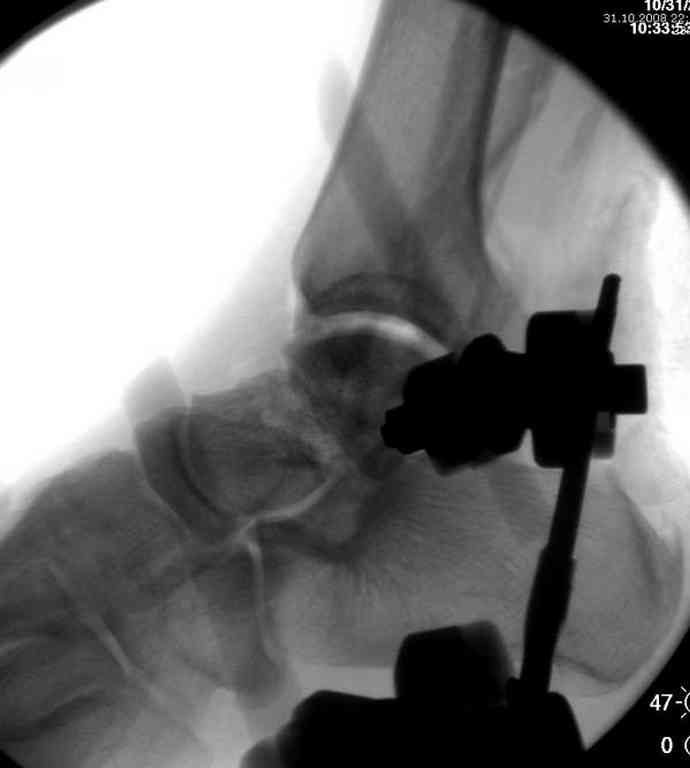

Второй случай прооперирован вчера.

10 дней назад поступил с открытым повреждением медиальной лодыжки и переломо вывихом таранной кости. Ургентно сделана репозиция с наложением наружного фиксатора + Irrigation&Debridment.

Во время репозиции выявили повреждение заднего сухожилия м. тибиалис и задней большеберцовой артерии. Медиальную рану удалось закрыть частично и установлен вакуум.

Дважды провели Irrigation&Debridment с заменой вакуума.

Вчера провели фиксацию.

Из-за многооскольчатости дистальной части малоберцовой, где невозможно было провести фиксацию шурупами, перелом зафиксирован подпирающей пластиной, которая должна служить дополнением отсутствующей дистальной части малоберцовой (lateral cortex substitute).

Для стабильности два шурупа на синдесмоз.

Медиальную рану с приближенными краями продолжаем вакуумировать (KCI). Наружный фиксатор оставлен на пару недель, надеюсь, небольшая рана будет гранулировать и закроется без кожной пластики. Фиксация медиальной ложыжки не планируется.